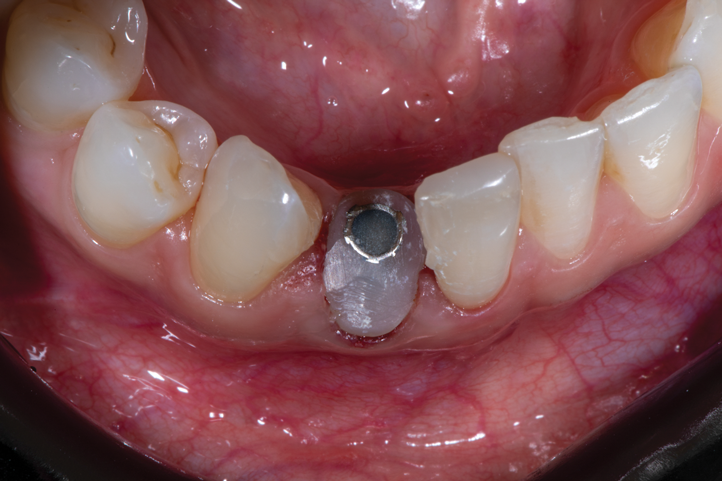

Fig 7. Finalized preparation utilizing the PET protocol, with implant placement in the No. 8 (1:1) position. An “S”-shaped chamfer preparation was made internally to the retained buccal portion of the root.

Figure 7

Fig 12. Implant placement No. 27 (4:3) after preparation of the root for PET protocol, demonstrating the ability to ideally place the implant within the newly prepared PET socket and maintain the integrity of the surrounding soft tissues.

Figure 12